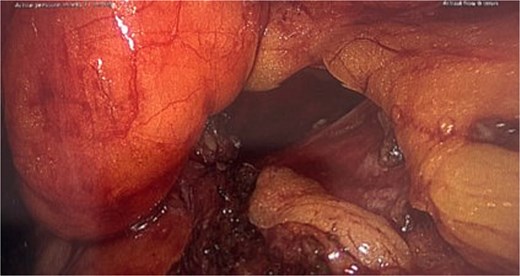

She proceeded for a laparoscopic TAPP excision of the hydrocele. After the abdominal cavity was entered and insufflated the preperitoneal flap was raised the hydrocele was identified medial to the inferior epigastric vessels (Fig. 2). With medial traction the hydrocele was able to be fully reduced and dissected free from the round ligament. The hydrocele was retrieved and sent for histological review. The resultant defect following excision (Fig. 3) was re-enforced with a 12 × 16 cm ProGrip mesh (Fig. 4) before the closure. She was observed post operatively and discharged home on the same day as her surgery.

Intraoperative picture following excision of the hydrocele demonstrating the resulting defect.

In up to one third of cases there is an associated inguinal hernia due to the widening of the internal ring [3]. Additionally, to excise the cyst intact may require widening of the neck hence Venkateswaran et al. [7] recommended that the posterior wall should be reinforced with a mesh regardless of the present of a hernia or not due to the future risk of herniation. In this case following excision of the sac this defect is clearly visible (Fig. 3) and would be expected to develop into a hernia if left untreated.